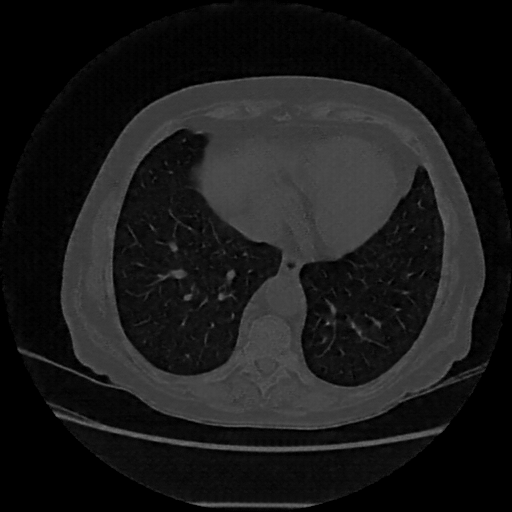

Original VENOUS CT scan

Lung window (WL -600, WW 1500 β†’ Low βˆ’1350, High +150)